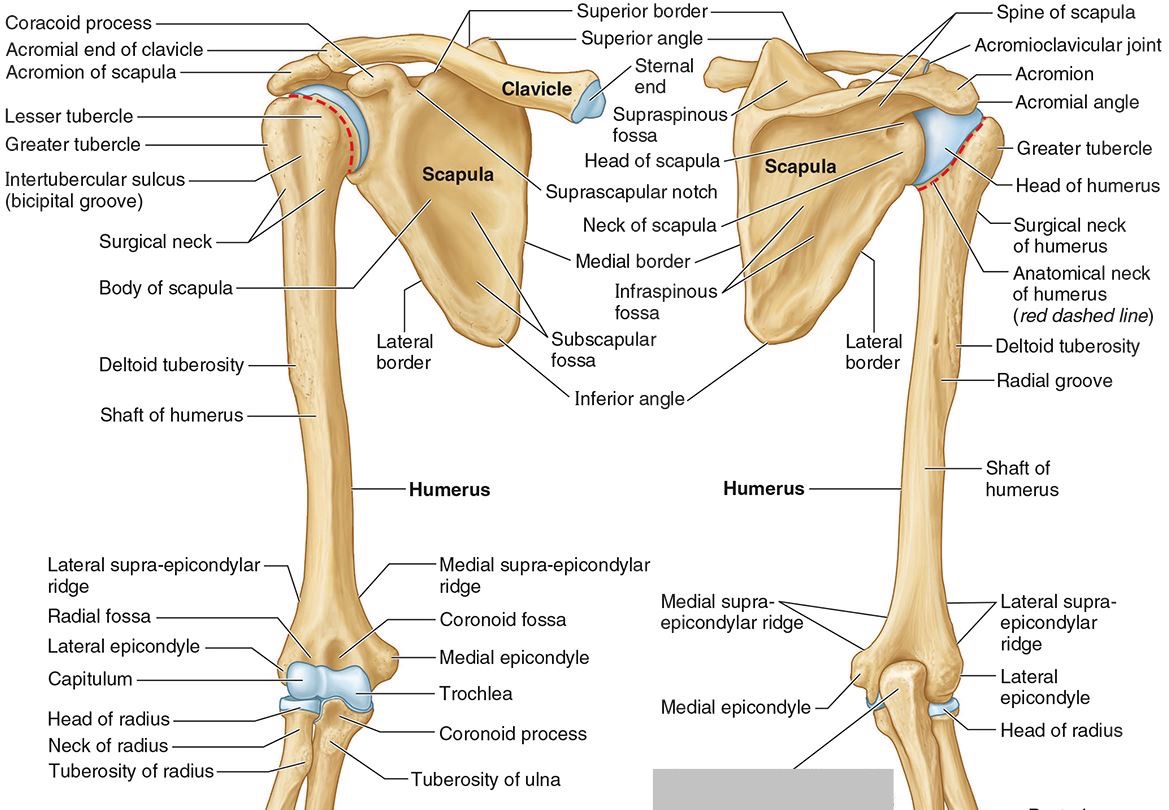

What part of the humerus is this?

The head of the humerus articulates with the scapula at the glenohumeral joint.

What part of the humerus is this?

The anatomic neck is an indentation distal to the head and provides an attachment for the fibrous joint capsule of the glenohumeral joint.

What part of the humerus is this?

The greater tubercle lies lateral and distal to the anatomic neck.

What part of the humerus is this?

The lesser tubercle lies on the anterior/medial side of the humerus, just distal the anatomic neck.

What part of the humerus is this?

The intertubercular (bicipital) groove lies between the greater and lesser tubercles.

What part of the humerus is this?

The surgical neck is a narrow area distal to the tubercles. It is a common site for proximal humerus fractures.

What part of the humerus is this?

The humeral shaft features the deltoid tuberosity laterally for the distal insertion of the deltoid muscle.

What part of the humerus is this?

The radial groove is an oblique depression that contains the radial nerve and deep brachial artery.

Which parts of the humerus is this?

The medial and lateral epicondyles are distal prominences to which many forearm tendons attach, near the elbow joint.

Which parts of the humerus is this?

The medial and lateral supracondylar ridges extend superiorly from the medial and lateral epicondyles.

Which parts of the humerus is this?

The trochlea and the capitulum (the condyles) are the most distal surfaces of the humerus, where it articulates with the forearm bones at the elbow joint

What part of the humerus is this?

The olecranon fossa is a posterior depression above the trochlea that receives that olecranon process of the ulna

What part of the humerus is this?

The coronoid fossa is an anterior depression above the trochlea that receives that coronoid process of the ulna.